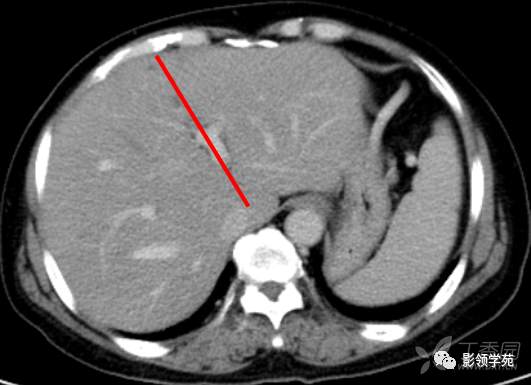

肝脏八段分法的影像学解剖示意图

第一肝门层面CT横断面解剖

CT:首先找出肝脏的三大静脉:肝中静脉,肝左静脉,肝右静脉,找出门静脉及其分叉部位。门静脉分叉部位可以区分上段和下段,即肝S8/S5,S7/S6,门静脉分叉以上为S8、S7;肝右静脉和肝中静脉之间是右前叶,肝右静脉以后是右后叶

一般规律,从CT上看,最先看到的是S8然后是S2、3,肝左外叶以肝裂为界,左内叶为肝裂和肝中静脉之间的区域,胆囊往下的层次是S5,最后的层面一般是S6,下腔静脉和门静脉夹着的是尾状叶,即S1。